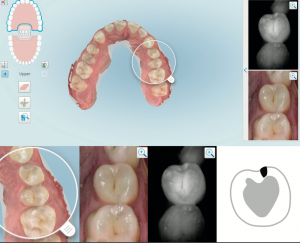

Uno dei principali vantaggi recati dallo scanner di ultima generazone è rappresentato dal NIRI, un sistema di emissione di raggi infrarossi che viene emesso contestualmente alla registrazione di video in Hd che consente di intercettare ogni lesione curiosa ancor prima che sia individuabile alle radiografie. E’ dunque possibile oggi trattare precocemente le lesioni che ancora sono in fase reversibile consentendo di preservare la sostanza dentale ed evitare l’uso del trapano.